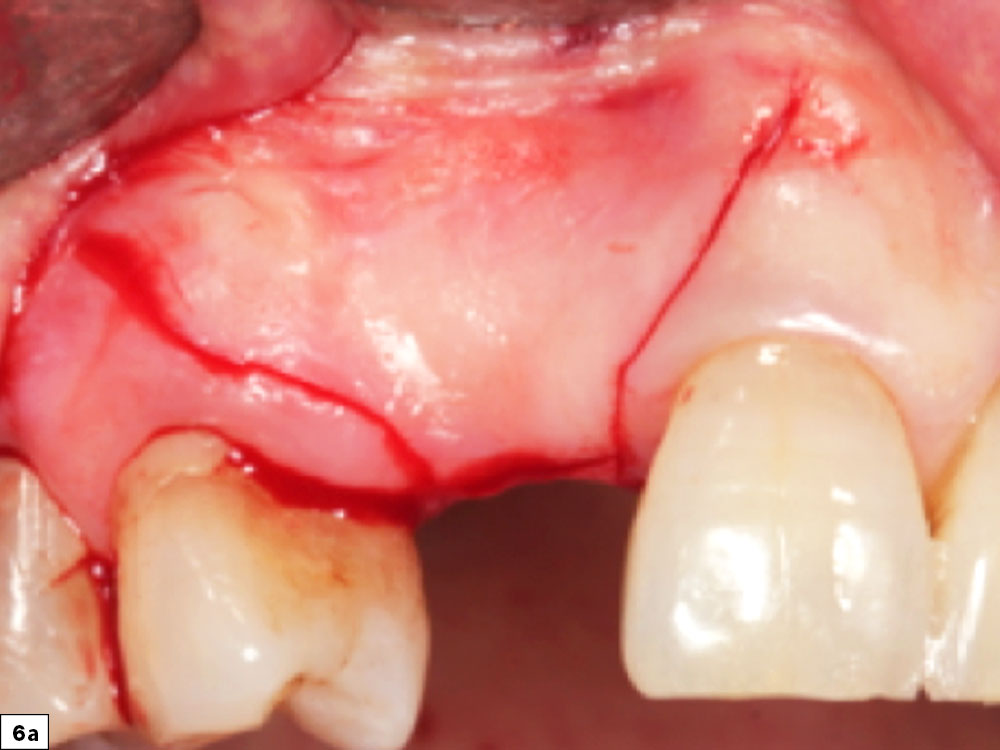

The coronal incision is usually positioned on the crest of the ridge, with a more palatal position if the amount of existing attached tissue is compromised. Vertical release incisions are made on the buccal surface and extend to the mucogingival junction. Broad-based incisions are important to prevent interruptions in the vascular supply to the flap and to allow for elevation, retraction, repositioning and suturing without tension. It is imperative that a continuous full-thickness incision be made on bone through the tissue and the periosteum. Incisions that are irregular may lead to maceration of the flap, which compromises the primary blood supply source (periosteal tissue layer). When incisions involve adjacent teeth, papillae-sparing incisions should be completed, leaving a minimum of 1 mm of the papilla intact (Figs. 6a, 6b).

Papillae-sparing incision maintains blood supply

Papillae-sparing incision prevents postoperative tissue recession

Figures 6a, 6b: Papillae-sparing incision depicting a broad-based design that maintains blood supply and prevents postoperative tissue recession.